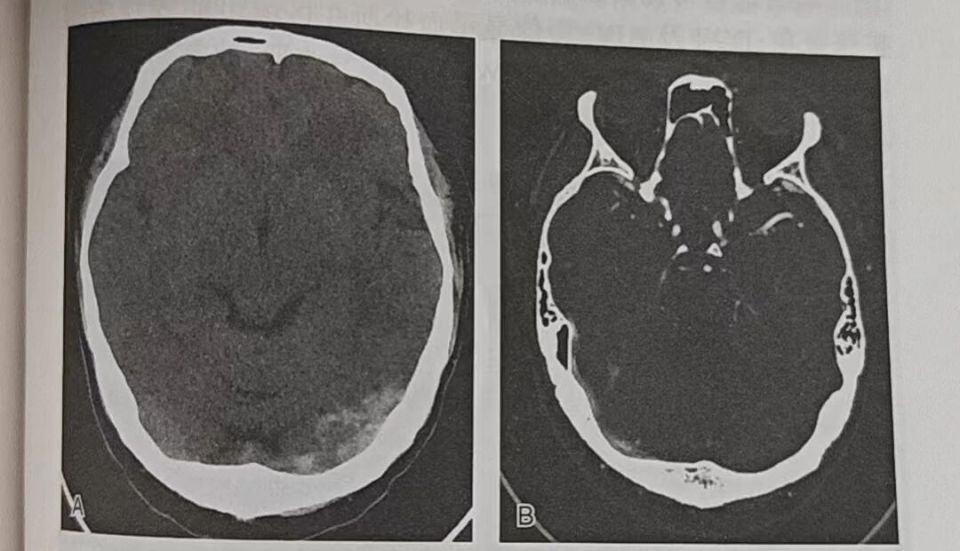

CT增强扫描:与CT常规平扫图像对比利于明确诊断。可见硬脑膜窦中心无强化呈低密度,周围硬脑膜强化呈高密度,即“Delta征”或“空三角征”,部分慢性血栓偶尔可见强化,但“Delta征”或“空三角征”也存在假阳性可能,如新生儿和真性红细胞增多症患者的硬脑膜静脉窦内亦可见高密度影。硬脑膜静脉窦血栓形成后CTV表现为硬膜窦内充盈缺损,窦壁增强及侧支引流增加(图1)。

图片

图1.左侧横窦及乙状窦内血栓形成影像学表现A.CT平扫显示左侧横窦区高密度影;B.注射对比剂后左侧横窦结构缺